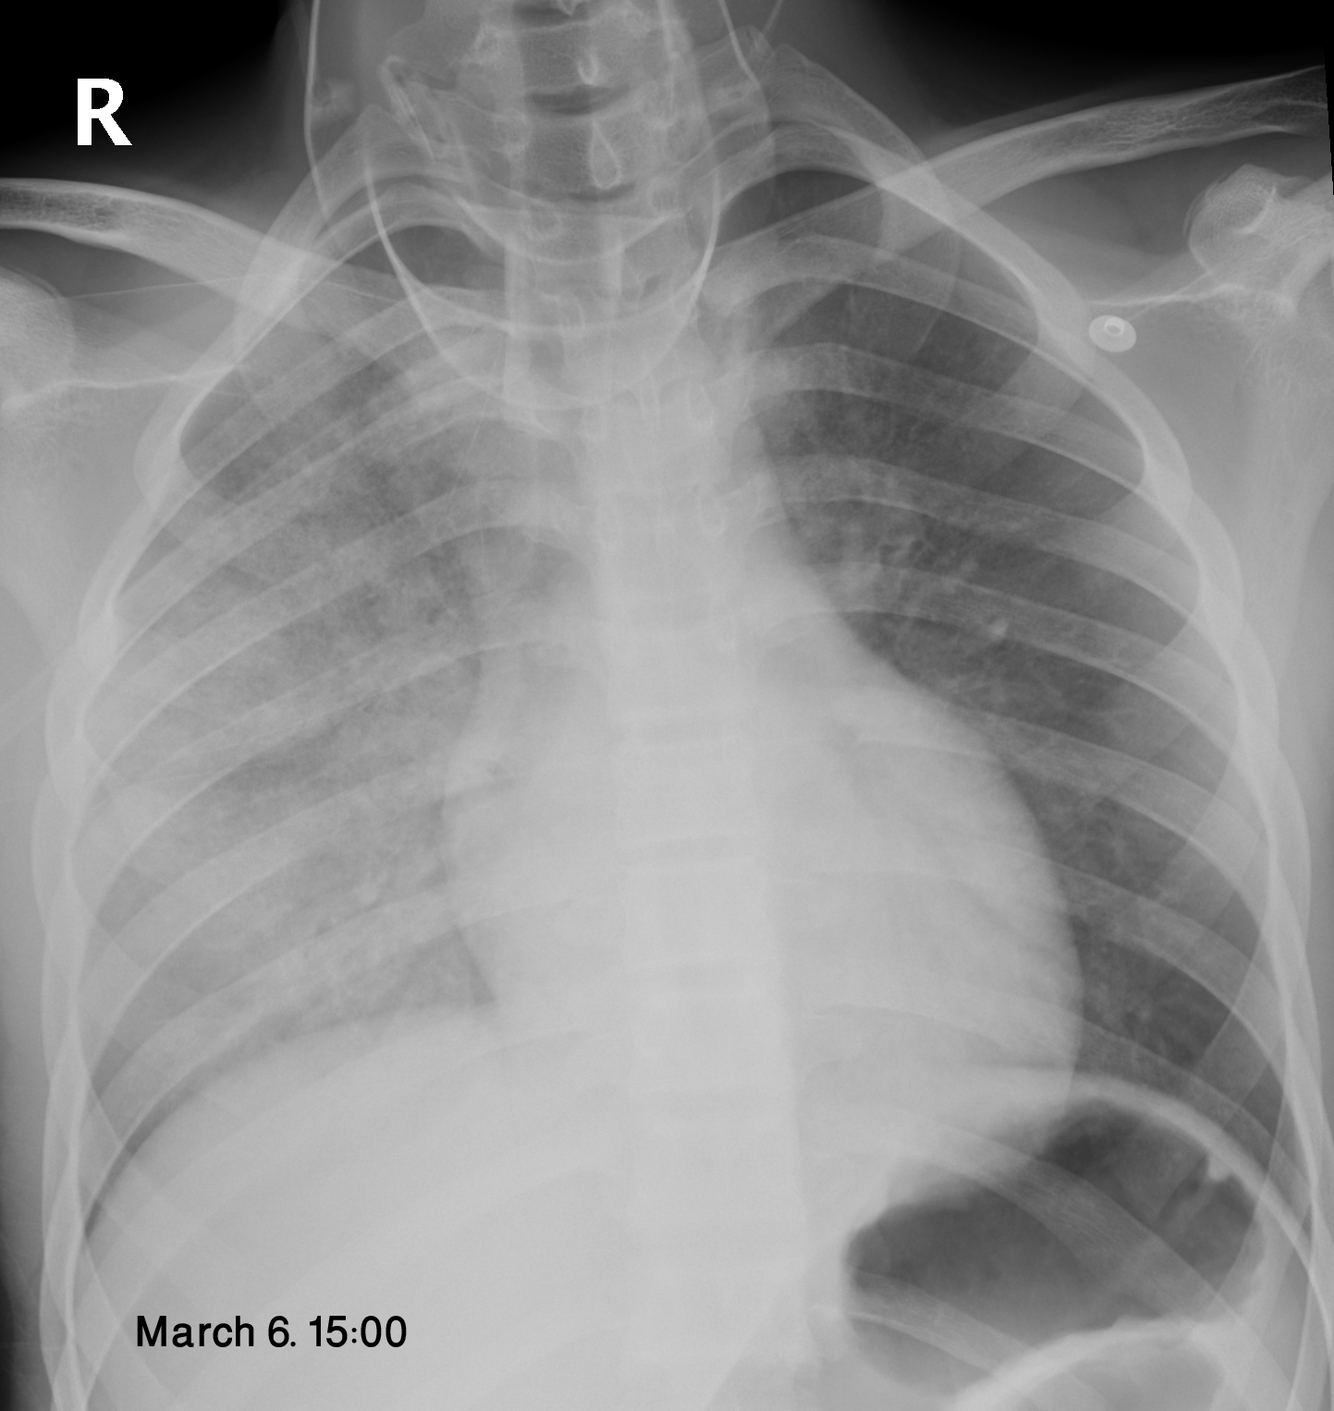

What is re-expansion pulmonary edema?

Pulmonary edema developing following rapid re-expansion of a lung collapsed by pneumothorax or large effusion (especially if it was collapsed > 72 hours). Edema can rarely be bilateral.